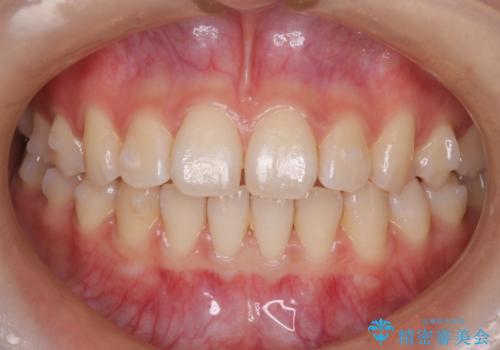

【前歯で噛めません、すきっ歯も気になります】インビザライン治療症例

- 前歯の見た目と噛み合わせの改善を希望され来院された患者様です。

初診時の歯並びの状態としては、上下前歯が噛んでいない開口という状態であり、前歯を中心に上下とも歯の間に隙間がある状態でした。

抜歯は行わずマウスピース治療による主訴の改善を計画しました。

見た目、嚙み合わせ及び、治療期間や施術内容に大変ご満足いただきました。